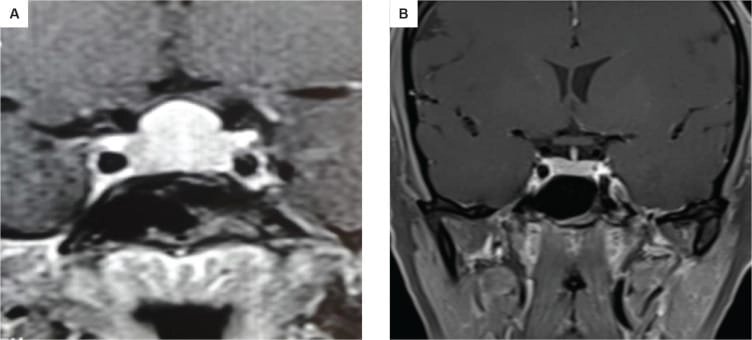

তবে পিটুইটারি হাইপারপ্লাসিয়া দেখা যায় প্রাইমারি গনাডাল, অ্যাডরিনাল বা হাইপোথাইরয়েডিজমের মত এন্ড অর্গান ইনসাফিসিয়েন্সিতে। বিশেষ করে, অব্যবহৃত প্রাইমারি হাইপোথাইরয়েডিজমে পিটুইটারি হাইপারপ্লাসিয়া পূর্বের ধারণার তুলনায় অনেক বেশি দেখা যায়। ২০১৯ সাল পর্যন্ত এরকম ১০৫টি কেস রিপোর্ট করা হয়েছে। এই ধরনের হাইপারপ্লাসিয়া গম্বুজ-আকৃতির (dome-shaped) হয়ে অপটিক কায়াজমাকে চেপে ধরতে পারে, যার ফলে অপারেশনের প্রয়োজন পড়তে পারে—যেমনটা আমাদের তৃতীয় কেসে ঘটেছিল।

MRI-তে এই হাইপারপ্লাসিয়া সাধারণত গম্বুজ-আকৃতির ও সমমিত হয় এবং হোমোজেনাস সিগনাল ইন্টেনসিটি দেখায়, যেখানে সাধারণ নন-ফাংশনাল পিটুইটারি অ্যাডেনোমা নানা আকার ও অসমতা নিয়ে দেখা যায়।

তাঁর দাবি, MRI-তে ‘DOME Sign’ থাকা এবং TSH বাড়তি থাকলে, সেটি হাইপোথাইরয়েডিজম-জনিত হাইপারপ্লাসিয়ার সম্ভাবনার কথা নির্দেশ করে এবং এই রোগীদের শুধুমাত্র লেভোথাইরক্সিন দিয়ে চিকিৎসা করলে পূর্ণ আরোগ্য সম্ভব।